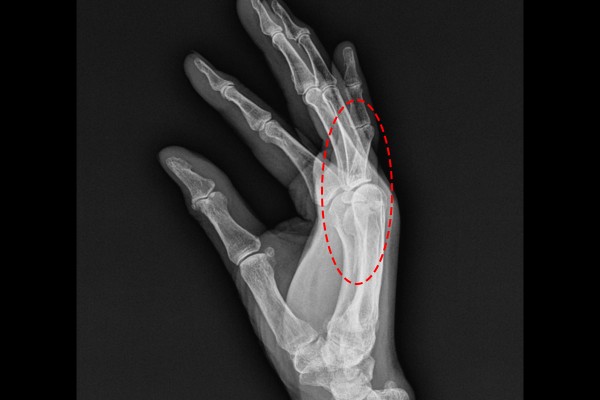

70세 여성 환자분께서 우측 손 골절 증상으로 내원해주셨습니다. 환자분께서는 소를 키우시고 계신데, 내원 전날에 소 밧줄에 손이 감기면서 다치셨고, 손날 부분이 골절된 것 같다고 말씀하셨습니다. 육안으로 볼 때도 새끼손가락이 위로 꺾여있는 것이 확인되었고, 정확한 상태 파악을 위해 X-RAY 촬영을 진행하였습니다.

X-RAY 촬영 결과, 새끼손가락 중수골과 근위지골이 골절된 것이 확인되었습니다.

측면에서 확인했을 때, 중수골, 근위지골 골절로 새끼손가락이 위로 꺾인 것을 확인하여 우측 손 중수골 및 새끼손가락 골절(Fx. 5th Metacarpal neck + 5th prox.phal hand Rt.)을 진단하였습니다.